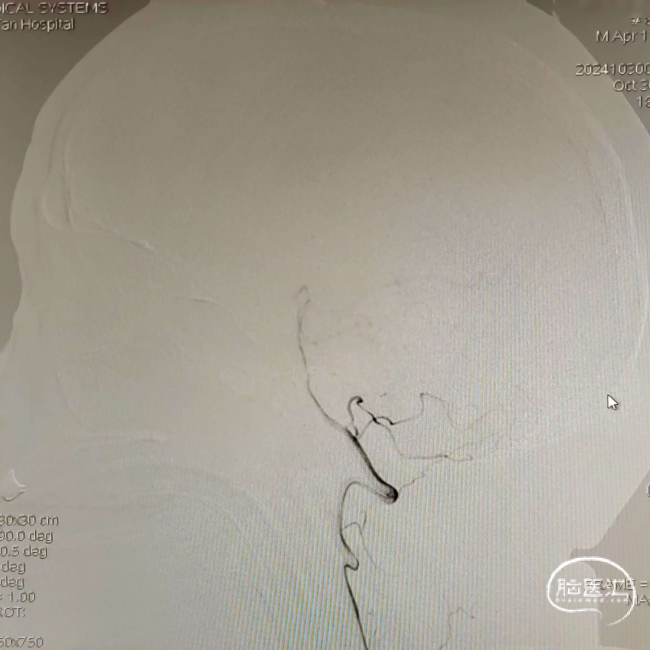

左侧颈内动脉造影见左侧大脑中动脉M1段重度狭窄,左侧大脑前动脉显影浅淡。

多角度投照,通过中间导管造影,可见左侧大脑中动脉M1段重度狭窄,狭窄约85%以上。

沿5F 115cm 通桥银蛇®PLUS远端通路导管将北斗SS™ 3m标准版微导丝小心通过狭窄段后送至M2远端,再沿微导丝送入颅内球囊扩张导管 2.0*9mm至狭窄段,造影确认定位准确,球囊缓慢加压至6atm,持续10s后抽瘪球囊,共球扩2次。

将球囊缓慢退至中间导管内,造影可见狭窄处明显改善,前向血流好,分支显影清晰,残余狭窄约10%。

观察10分钟后,将5F 115cm 通桥银蛇®PLUS远端通路导管退至6F长鞘内,正侧位造影见左侧大脑中动脉前向血流好,血流稳定,狭窄段未见弹性回缩,远端分支血管无急性闭塞征象,结束手术。